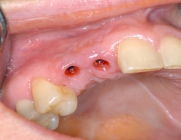

Since 1992, titanium screw implants have been inserted in edentulous sections of the upper and lower jaw in the clinic. Such dental implants serve as artificial tooth roots which, in combination with a tooth-crown-like superstructure (superstructure), enable the restoration of isolated tooth gaps with a crown, in the case of several missing teeth with a crown block, and finally in the case of an edentulous jaw with a fixed prosthesis.

During the consultation, a clinical examination of the existing teeth, the jaws and an analysis of the X-ray images is performed. These exploratory examinations and an additional interview with the patient can determine the extent to which the placement of implants is possible in the respective individual situation and also exclude factors that would impair the chances of success of implant placement.

One of the prerequisites for a successful and durable implant restoration is sufficient height and width of the remaining jaw bone. A special focus of the clinic is to create a favorable implant site for implantation by depositing autologous bone or bone substitute materials in the maxilla by introducing the bone into the maxillary sinus.